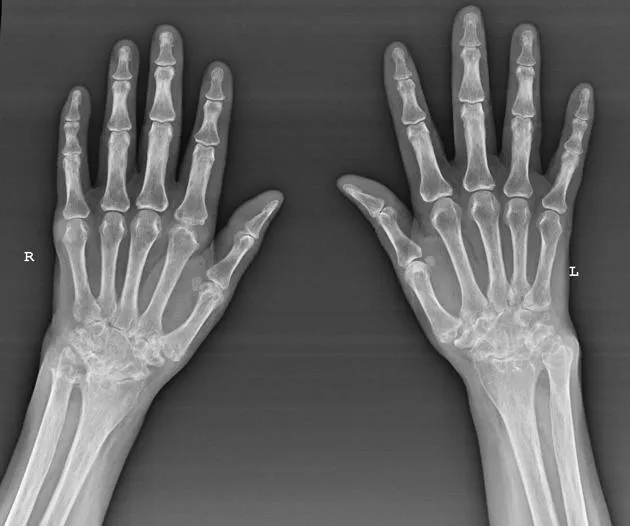

A 52-year-old woman presents with bilateral hand pain and morning stiffness lasting 90 minutes. Her metacarpophalangeal joints are swollen and tender. This clinical picture immediately raises suspicion for inflammatory arthritis, specifically , where early recognition transforms outcomes. Meanwhile, in the haematology clinic, a 68-year-old man's routine bloods reveal haemoglobin of 92 g/L with microcytosis-triggering a systematic approach to . These scenarios exemplify the precision required in rheumatological and haematological diagnosis.

Rheumatoid arthritis exemplifies autoimmune-driven inflammation. Genetic susceptibility (HLA-DR4) combines with environmental triggers (smoking, infection) to breach immune tolerance. Anti-citrullinated protein antibodies (anti-CCP) target synovial proteins, initiating complement activation and cytokine release-particularly TNF-α, IL-6, and IL-1. This inflammatory cascade drives synovial hyperplasia, pannus formation, and cartilage destruction. Understanding this pathway explains why early DMARD therapy in prevents irreversible joint damage within the critical 3-month window.

Early aggressive DMARD therapy in follows NICE NG100: methotrexate 15-25 mg weekly with folic acid 5 mg weekly (not on methotrexate day) is first-line. Treatment target is remission (DAS28 <2.6) or low disease activity. Failure after 3 months at therapeutic dose warrants escalation to dual/triple DMARD or biologic therapy (anti-TNF, rituximab, tocilizumab). For VTE , NICE NG158 recommends DOACs (apixaban 10 mg BD for 7 days, then 5 mg BD) over warfarin for most patients.